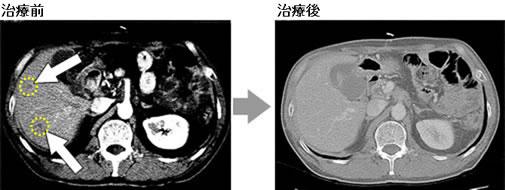

NK免疫细胞疗法与手术+抗癌剂联合治疗,原发病灶几乎完全消失,肿瘤标志物降至正常。

治疗前 治疗后

2008年2月中旬,患者进行了4次NK免疫细胞治疗+抗癌剂后,主治医师进行了肿瘤标志物检查,肿瘤标志物(CA19-9)的数值在治疗开始之前为5,171,结束1个疗程后降至了28,已恢复正常值。

接受8次NK免疫细胞疗法+抗癌剂,癌症好转,原发病灶几乎完全消失

2008年4月,患者在持续进行病情观察和继续接受NK免疫细胞疗法+抗癌剂的第2疗程后,CT检查显示原发病灶几乎完全消失,肝转移的3个肿瘤中的2个肿瘤已经消失,剩下的那1个也缩小了,患者重新回归到了家庭生活当中。